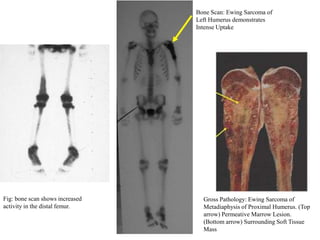

Bone Scan: Ewing Sarcoma of

Left Humerus demonstrates

Intense Uptake

Fig: bone scan shows increased     Gross Pathology: Ewing Sarcoma of

activity in the distal femur.      Metadiaphysis of Proximal Humerus. (Top

arrow) Permeative Marrow Lesion.

(Bottom arrow) Surrounding Soft Tissue

Mass

   Bone scan:

◦ To detect polyostotic involvement

◦ to detect bone metastasis